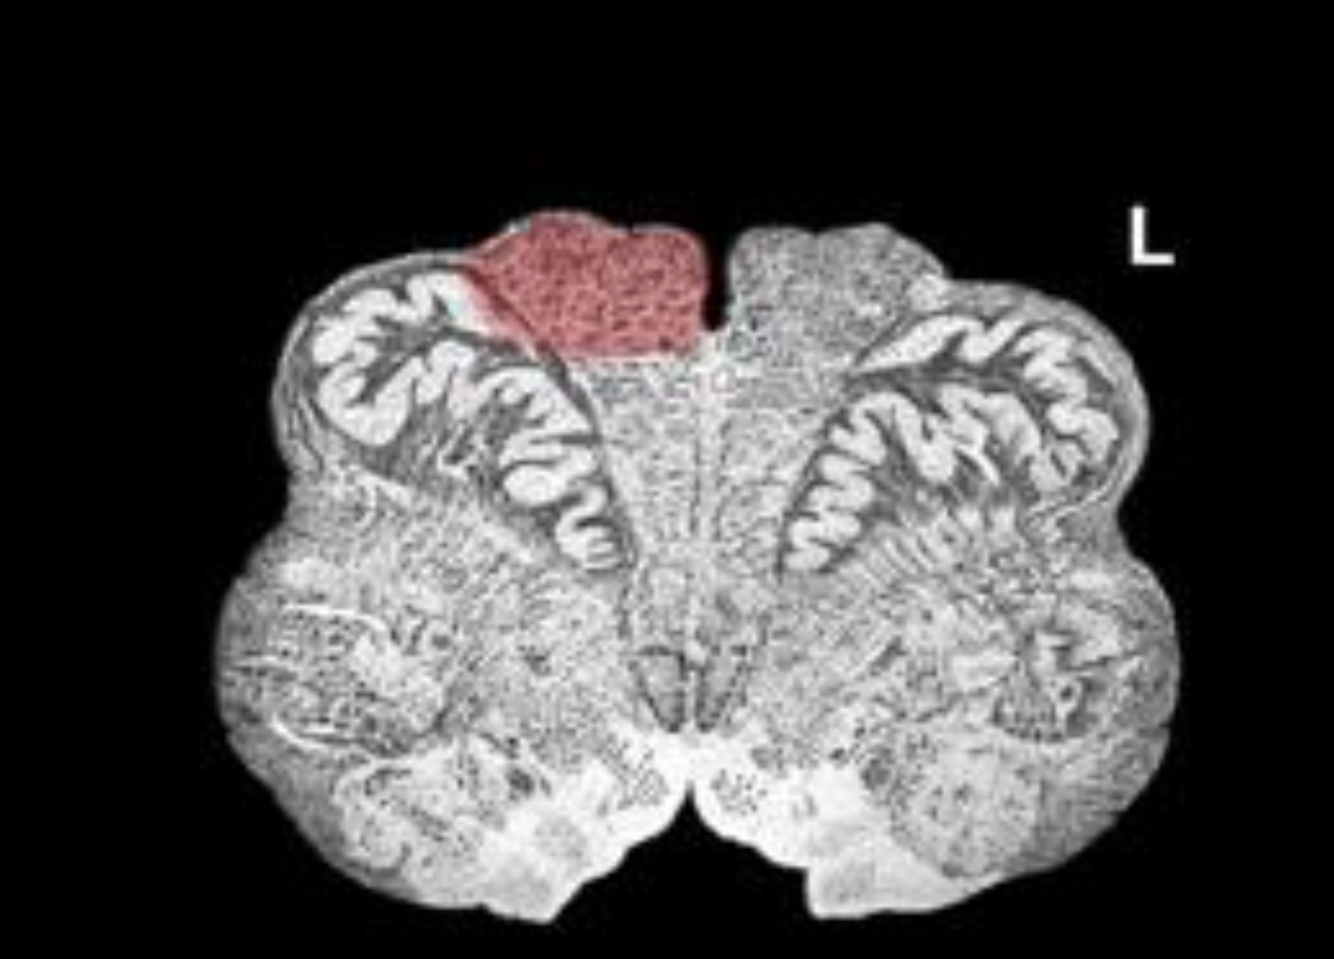

What is the name/location/results of the condition caused by a lesion in the shaded area?

Medulla, mid olive.

Right alternating hypoglossal hemiplegia

1) Destruction of the hypoglossal nerve results in ipsilateral paralysis of the muscles of the tongue, and atrophy of the ipsilateral muscles of the tongue

2) Destruction of the corticospinal tract at this level results in contralateral spastic hemiplegia

lesion is at the Medulla, mid olive.

atrophy/paralysis of tongue, deviates to the right

Spastic paralysis on left side of the body

loss of 2 pt tactile/proprioception on left sid of the body